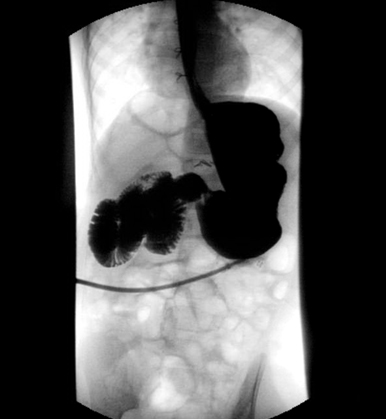

Enema: um enema de bário é útil para o diagnóstico de atresia do intestino delgado ou da doença de Hirschsprung; um enema diagnóstico pode ser usado para auxiliar no diagnóstico de intussuscepção e também agir como intervenção terapêutica.[Figure caption and citation for the preceding image starts]: Enema de bário com zonas de transição em pacientes com doença de HirschsprungDos acervos do Dr. R.A. Gomez-Suarez e Dr. J.E. Fortunato; usado com permissão [Citation ends].